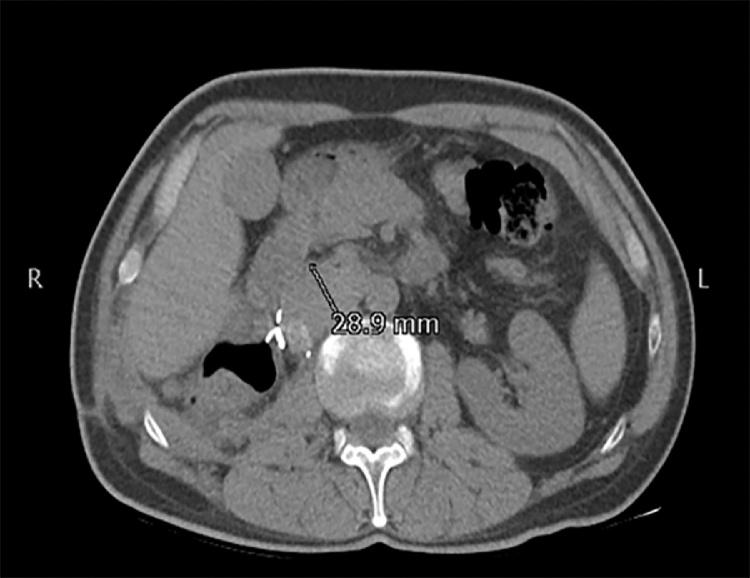

We present a case of a 50-year old male presented to the consulting clinics of a University Hospital with right flank pain since the last 2 months. The Computed Tomography (CT) and biopsy on the right renal mass indicated clear cell type renal cell carcinoma with significant lymphadenopathy. Past history of cystic lung disease and pneumothorax along with positive finding of renal cell carcinoma on CT and biopsy suggested Birt-Hogg-Dub́e (BHD) syndrome. The patient underwent right radical nephrectomy and lymph node dissection. His 3 months post- surgery follow up CT scan indicated disease recurrence.

我们展示了一例50岁男性患者,他在过去两个月里因右侧胁腹疼痛到一家大学医院的咨询门诊就诊。对右侧肾肿块进行的计算机断层扫描(CT)和活检显示为透明细胞型肾细胞癌,并伴有明显的淋巴结病。既往有囊性肺病和气胸病史,同时CT和活检发现肾细胞癌呈阳性,提示为Birt-Hogg-Dubé(BHD)综合征。该患者接受了右侧根治性肾切除术和淋巴结清扫术。术后3个月的CT扫描显示疾病复发。